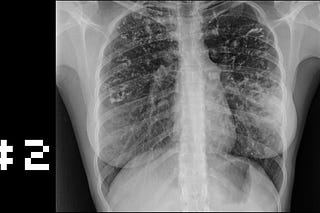

Issue #2 - The Disease That Never Really Paused

It’s World TB Day